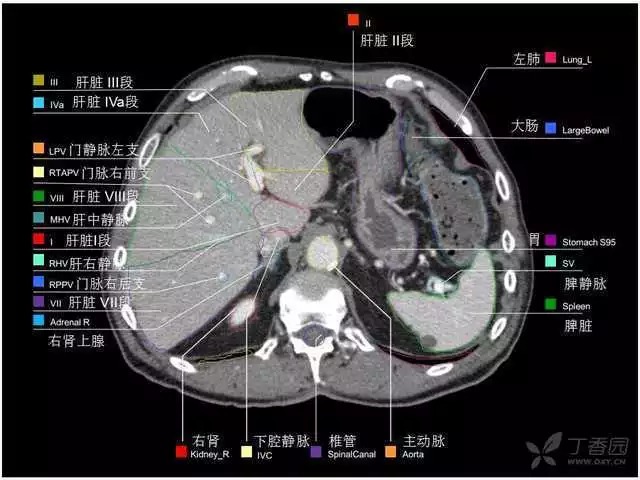

腹部肝脏高清CT断层的图谱

全腹部高清CT图谱,淋巴结彩色图谱,血管解剖图谱大汇总!

超声肝脏分叶及分段

肝脏分段和基本解剖学标志